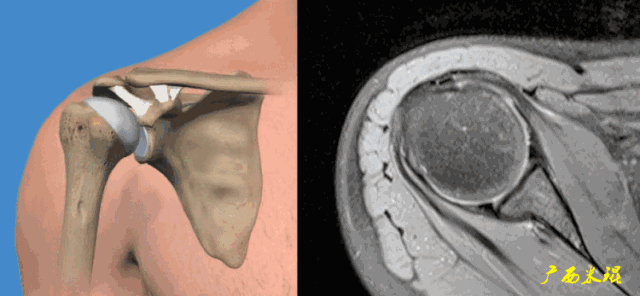

3、轴位:平行于关节盂/垂直于盂肱关节,主要评估盂唇,同时兼顾肩胛下肌、冈下肌及小圆肌。

各个序列肩袖均表现为均匀的低信号,是肌腱的延续。

Grade0:肩袖形态正常,连续性完好,肩袖信号正常。

Grade1:肩袖形态正常,连续性完好,肩袖内信号异常。

Grade2:肩袖连续性存在,形态异常(肩袖变薄/变厚,形态不规则)。

Grade3:肩袖外形异常,连续性中断。

在Zlaikin分级中,0级是正常肩袖,1、2级代表退变,3级为撕裂,也就是真正的肩袖损伤。